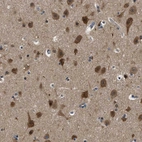

Immunohistochemistry analysis in human cerebral cortex and skeletal muscle tissues using HPA018954 antibody. Corresponding YARS RNA-seq data are presented for the same tissues.